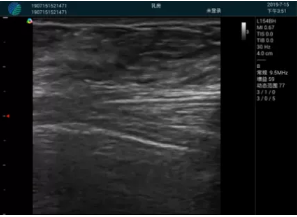

甲狀腺囊性結(jié)節(jié),囊壁鈣化,透聲好

甲狀腺囊性占位